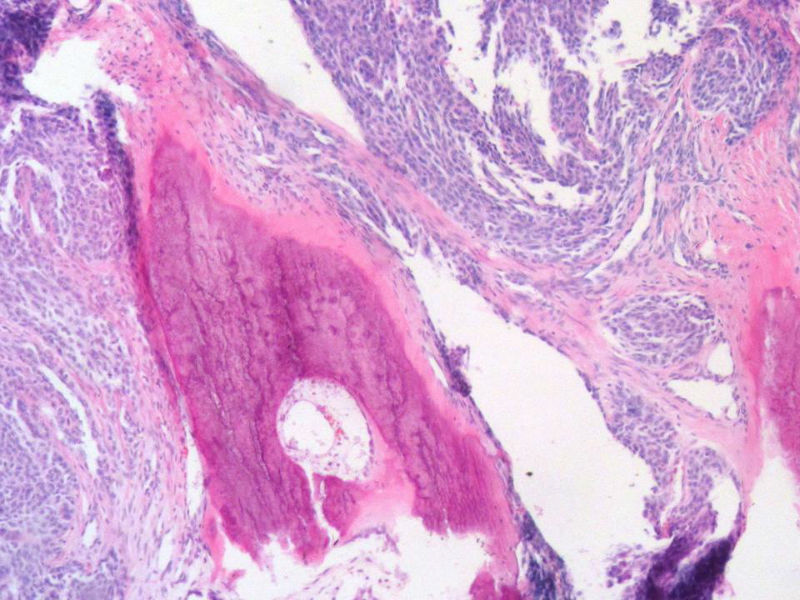

女,64岁,头晕半月,CT检查颅内左颞叶占位,侵犯颅骨和颞肌,手术切除肿物。肉眼,灰白色结节状肿物,3X3X2厘米,边界不清,切面灰黄色,质软。

特别提示:手术前曾做过介入肿瘤栓塞。镜下核分裂15/HP。脑左颞部占位图1

请教:本例患者曾做过介入肿瘤栓塞,图片内的坏死改变应该归为栓塞性梗死,还是肿瘤性坏死?两者形态上有区别吗?

梭形细胞与上皮样漩涡状结构,富于细胞,见个别沙砾体,并见肿瘤性坏死。颅骨及其横纹肌等软组织内见肿瘤呈侵袭性生长。但细胞异型性不是很大。鉴别:

1)恶性脑膜瘤

2)非典型性脑膜瘤

由于非典型性脑膜瘤也可以发生地图状坏死,甚至侵袭性生长。需要计数核分裂数/10HPF,以资鉴别诊断。